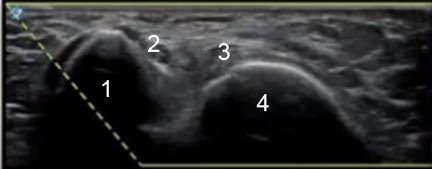

Elbow Ulnar Nerve Image

Medial Epicondyle

Ulnar Nerve

Medial Head of the Triceps

Olecranon Process